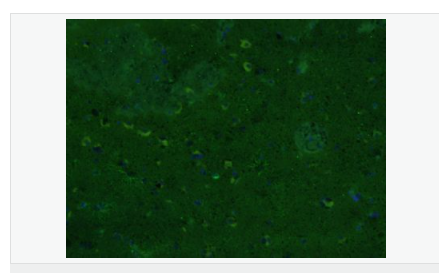

| 產(chǎn)品應(yīng)用 | WB=1:500-2000 ELISA=1:5000-10000 IHC-P=1:200-1000 IHC-F=1:200-1000 Flow-Cyt=1μg/Test ICC=1:100 IF=1:200-800 (石蠟切片需做抗原修復(fù)) not yet tested in other applications. optimal dilutions/concentrations should be determined by the end user. |

| 產(chǎn)品介紹 | This gene encodes one of the major intermediate filament proteins of mature astrocytes. It is used as a marker to distinguish astrocytes from other glial cells during development. Mutations in this gene cause Alexander disease, a rare disorder of astrocytes in the central nervous system. Alternative splicing results in multiple transcript variants encoding distinct isoforms. [provided by RefSeq, Oct 2008] Function: GFAP, a class-III intermediate filament, is a cell-specific marker that, during the development of the central nervous system, distinguishes astrocytes from other glial cells. Subunit: Interacts with SYNM. Isoform 3 interacts with PSEN1 (via N-terminus). Subcellular Location: Cytoplasm. Note=Associated with intermediate filaments. Tissue Specificity: Expressed in cells lacking fibronectin. Post-translational modifications: Phosphorylated by PKN1. DISEASE: Defects in GFAP are a cause of Alexander disease (ALEXD) [MIM:203450]. Alexander disease is a rare disorder of the central nervous system. It is a progressive leukoencephalopathy whose hallmark is the widespread accumulation of Rosenthal fibers which are cytoplasmic inclusions in astrocytes. The most common form affects infants and young children, and is characterized by progressive failure of central myelination, usually leading to death usually within the first decade. Infants with Alexander disease develop a leukoencephalopathy with macrocephaly, seizures, and psychomotor retardation. Patients with juvenile or adult forms typically experience ataxia, bulbar signs and spasticity, and a more slowly progressive course. Similarity: Belongs to the intermediate filament family. SWISS: P14136 Gene ID: 2670 Database links: Entrez Gene: 2670 Human Entrez Gene: 14580 Mouse Omim: 137780 Human SwissProt: P14136 Human SwissProt: P03995 Mouse Important Note: This product as supplied is intended for research use only, not for use in human, therapeutic or diagnostic applications. 星形膠質(zhì)細(xì)胞標(biāo)志物 (Astrocyte Marker) GFAP是一個56kDa的中間絲蛋白(intermediate filament,IF),在中樞神經(jīng)系統(tǒng)發(fā)育期是一個特異性的標(biāo)志物,以區(qū)別星形細(xì)胞和其它膠質(zhì)細(xì)胞。GFAP表達(dá)在皮層和海馬,急、慢性皮質(zhì)酮治療時表達(dá)減少。 GFAP可以和人、大鼠、小鼠的GFAP反應(yīng),在正常和腫瘤性的星形膠質(zhì)細(xì)胞陽性表達(dá),而神經(jīng)節(jié)細(xì)胞、神經(jīng)元、成纖維細(xì)胞、少突膠質(zhì)細(xì)胞和這些細(xì)胞來源的腫瘤細(xì)胞陰性表達(dá),主要用于星形膠質(zhì)瘤等中樞神經(jīng)系統(tǒng)腫瘤的診斷和鑒別診斷,GFAP的缺乏可導(dǎo)致AD病。 |